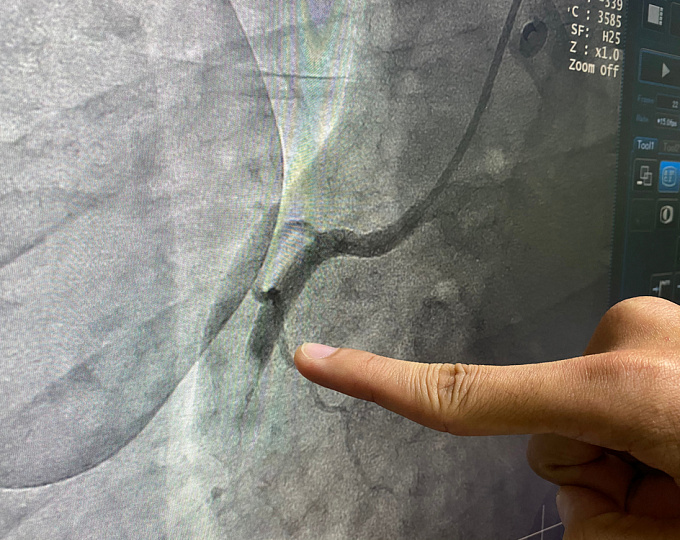

Целесообразность выполнения коронароангиографии (КАГ) у всех пациентов с инфарктом миокарда с подъемом сегмента ST (ИМспST) не вызывает сомнений.

Очевидно, что причиной остановки сердца во многих случаях является инфаркт миокарда. Следует ли всем таким пациентам (даже без верифицированного ИМспST) выполнять КАГ? Разобраться в этом вопросе и попытались авторы данного исследования.